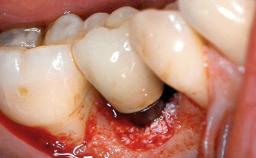

A 82-year-old female patient was referred to the Department of Oral Surgery and Stomatology at the University of Bern, Switzerland, for further diagnosis and treatment of growing discomfort in the right mandible (implant 45) and left maxilla (implant 23). The patient had had implants of various types inserted in the mandible and maxilla over the course of the previous three decades (in the 1980s and 1990s). The patient had received removable partial dentures on implants in the maxilla and on natural teeth in the mandible. The implants in the posterior right mandible had been restored with two splinted single crowns. The lower partial denture was not well tolerated by the patient and therefore had not been worn for over ten years. After insertion of the implants, there had been no complications for many years, but implants 45 and 46 as well as 23 had begun to exhibit signs of peri-implantitis with limited bone loss several years previously. The infection had been treated by the private practitioner, and bone loss around the three implants had not progressed until about half a year previously.